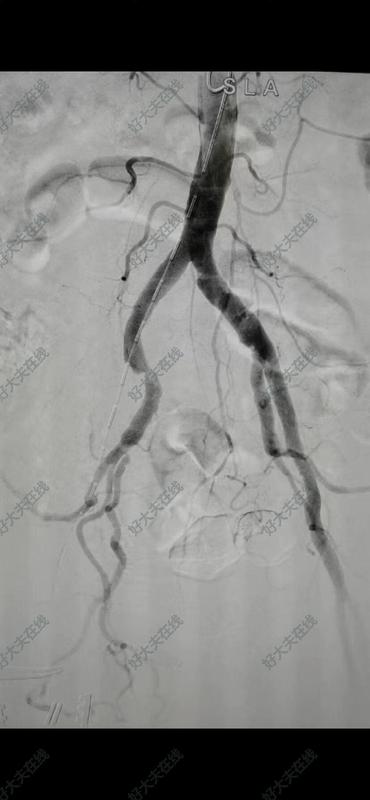

糖尿病足/下肢動脈硬化閉塞癥。

男性,80歲,因雙下肢發(fā)涼、麻木、跛行100米就診,糖尿病、吸煙史多年,診斷為下肢動脈硬化閉塞癥等,拒手術、口服藥物治療,期間足趾外傷破潰不愈,疼痛難寐,遂入院微創(chuàng)手術治療,開通閉塞血管,血供恢復,疼痛緩解。